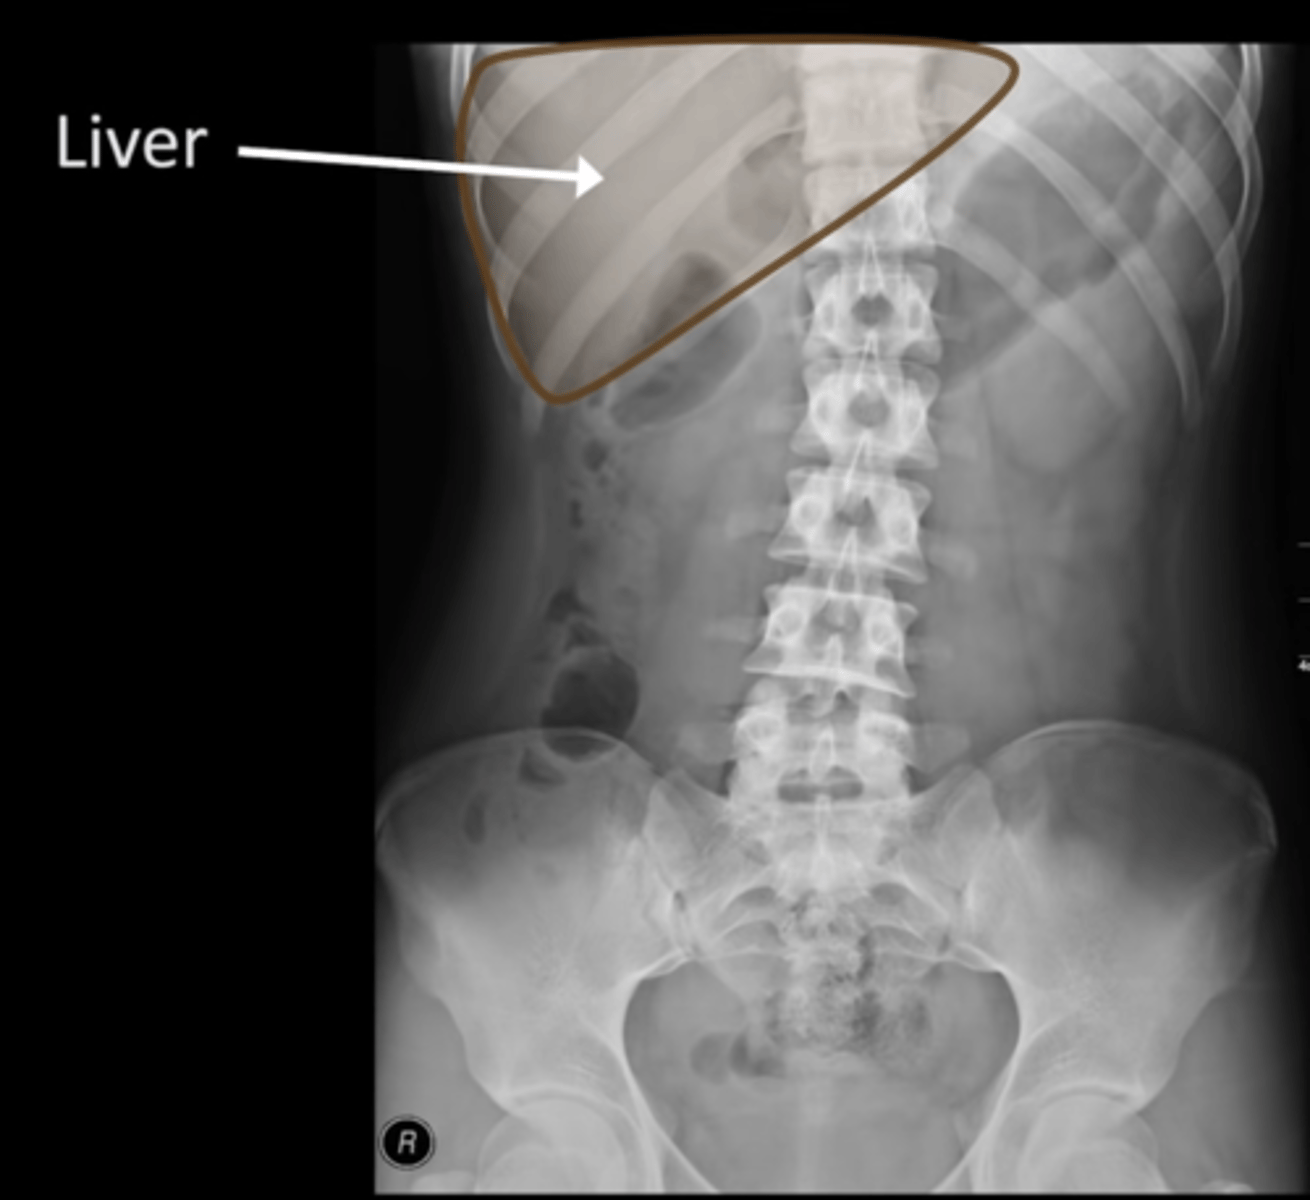

Normal AXR (and normal size liver)

Abnormal organs on AXR

Hepatomegaly